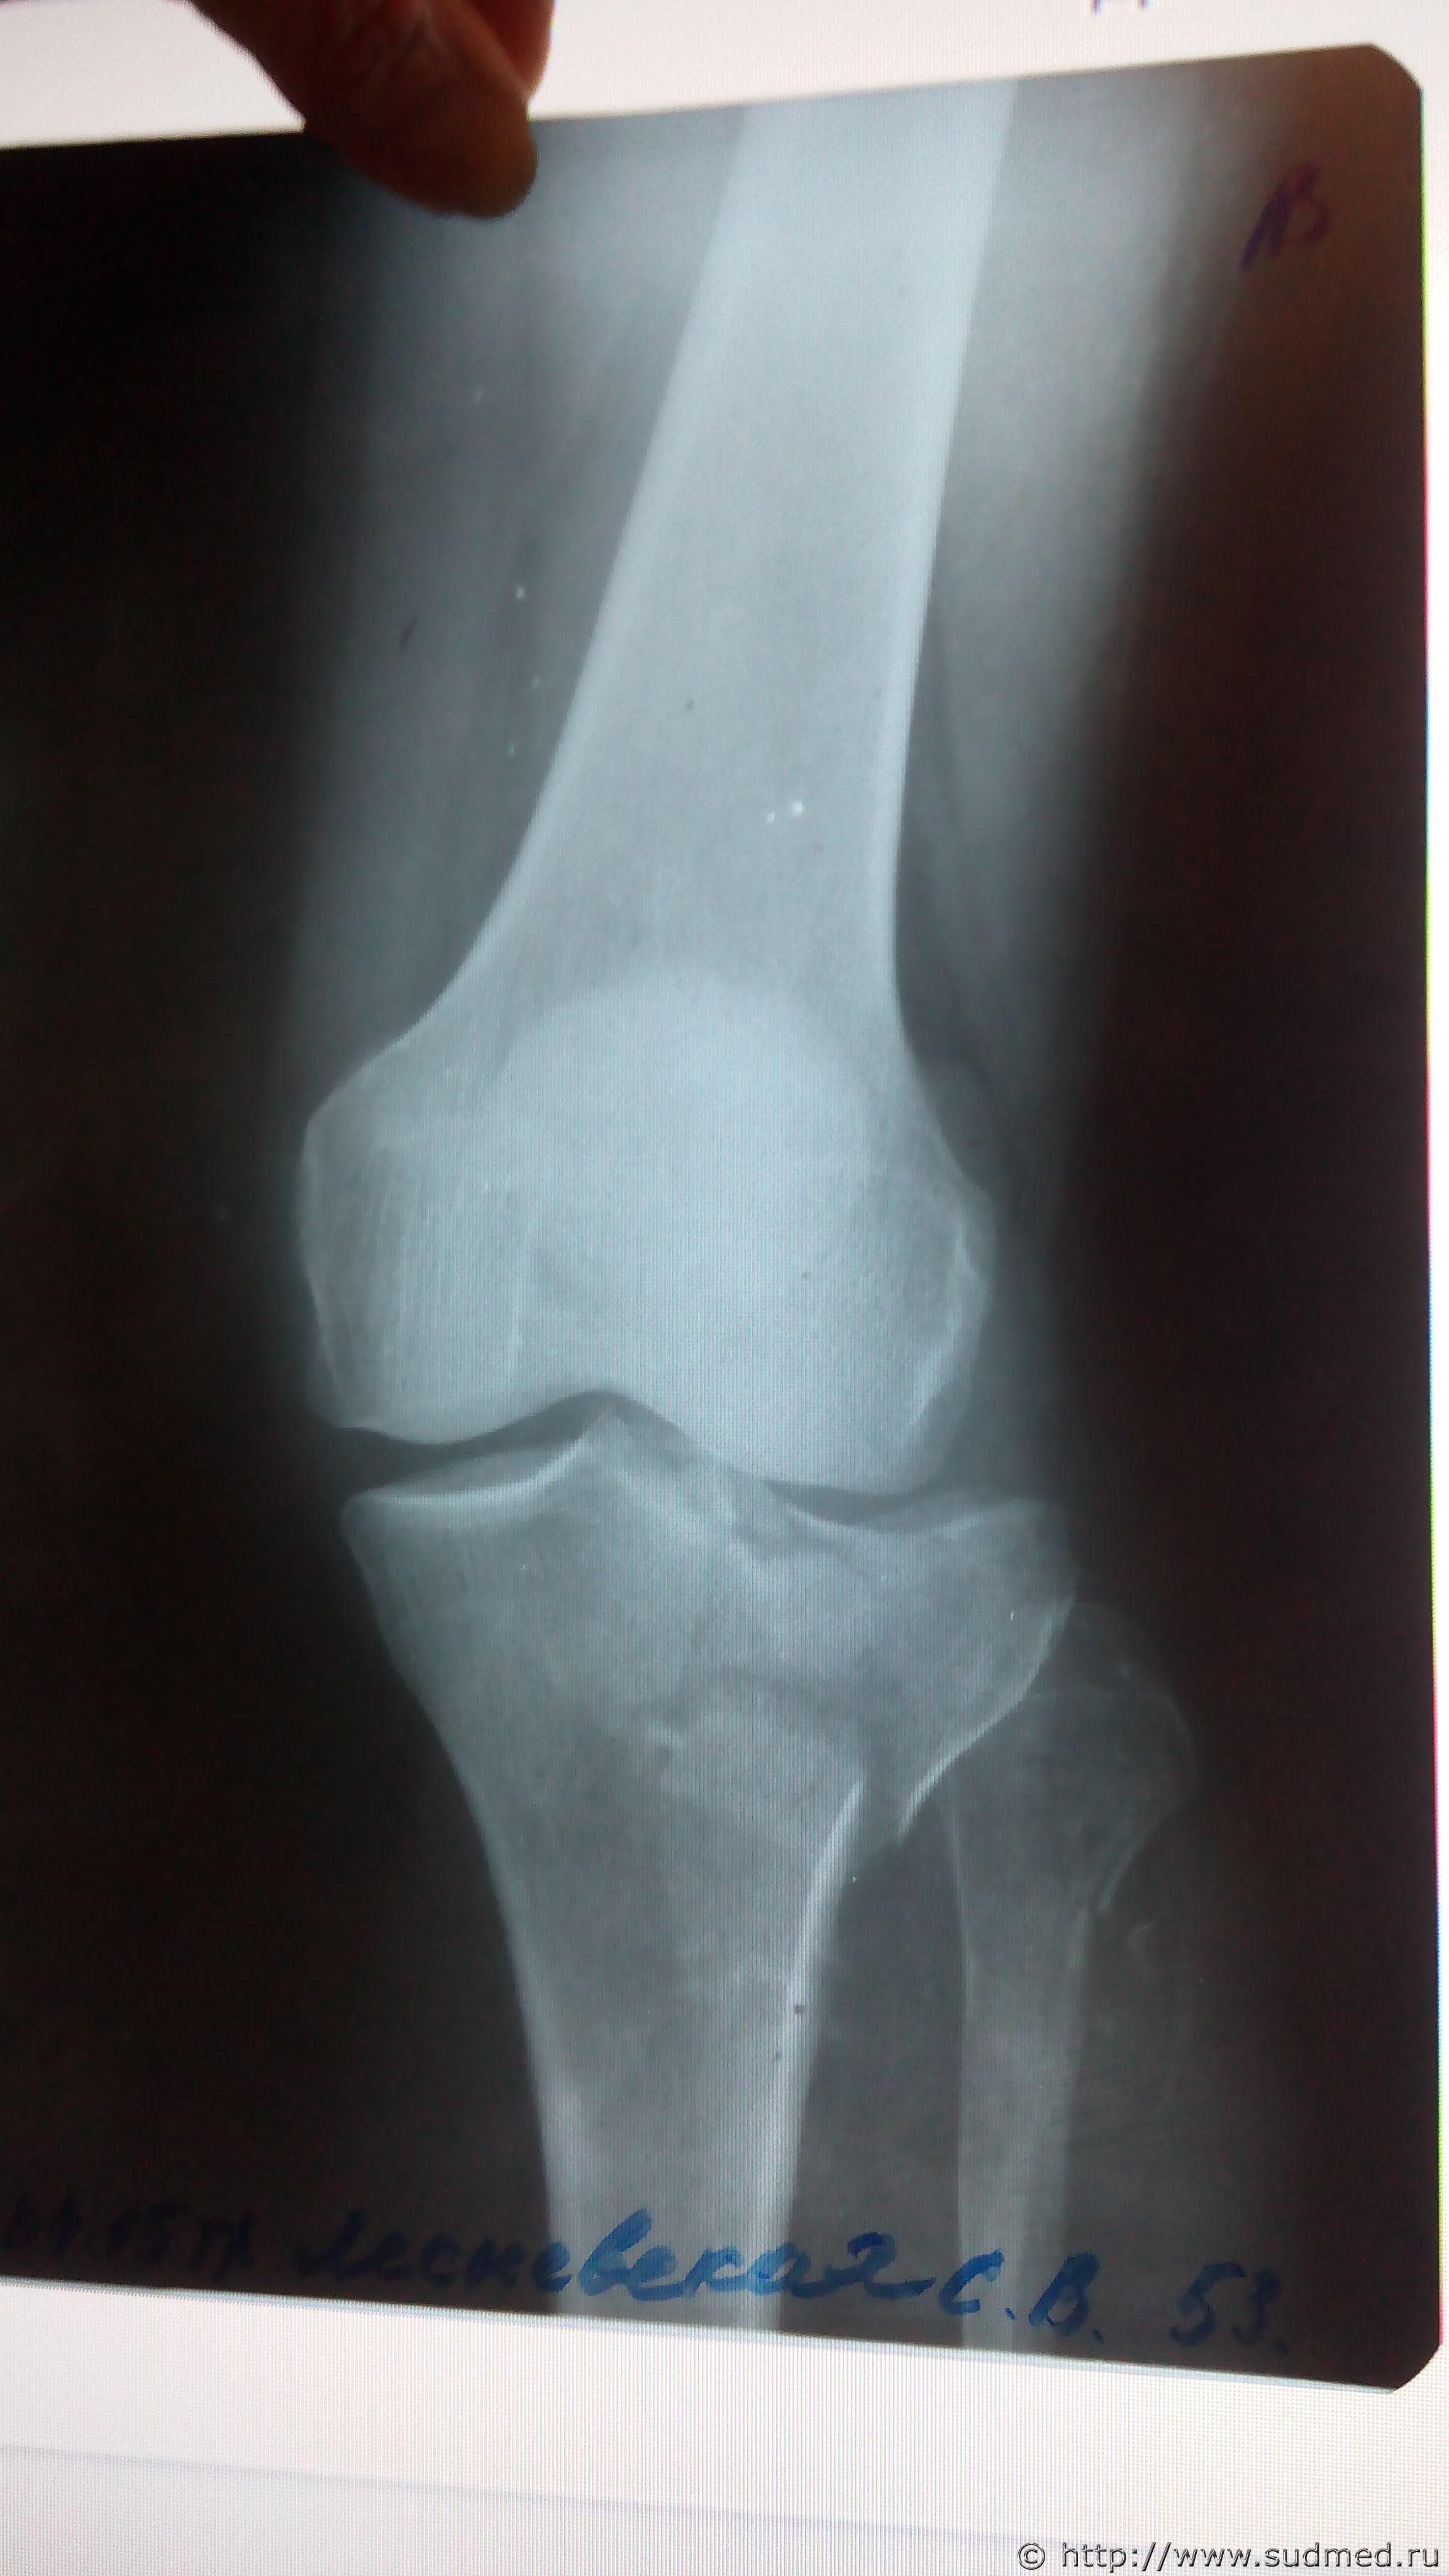

Первый рентген (до операции, 2 проекции) отсканировать есть возможность - давайте посмотрим.

Здравствуйте , постараюсь выложить снимки .

Эскизы прикрепленных изображений

Судебная медицина - Прикрепленное изображение

Выложите все снимки. Это может быть важно: если перелом большеберцовой кости распространяется на её диафиз, то может быть тяжкий вред (п.6.11.8 приложения к Приказу Минздравсоцразвития от 24.04.08г. №194н). На единственном выложенном Вами снимке этого не видно, но зона перелома - совсем рядом с диафизом. Хотелось бы разобраться, как все обстоит на самом деле.